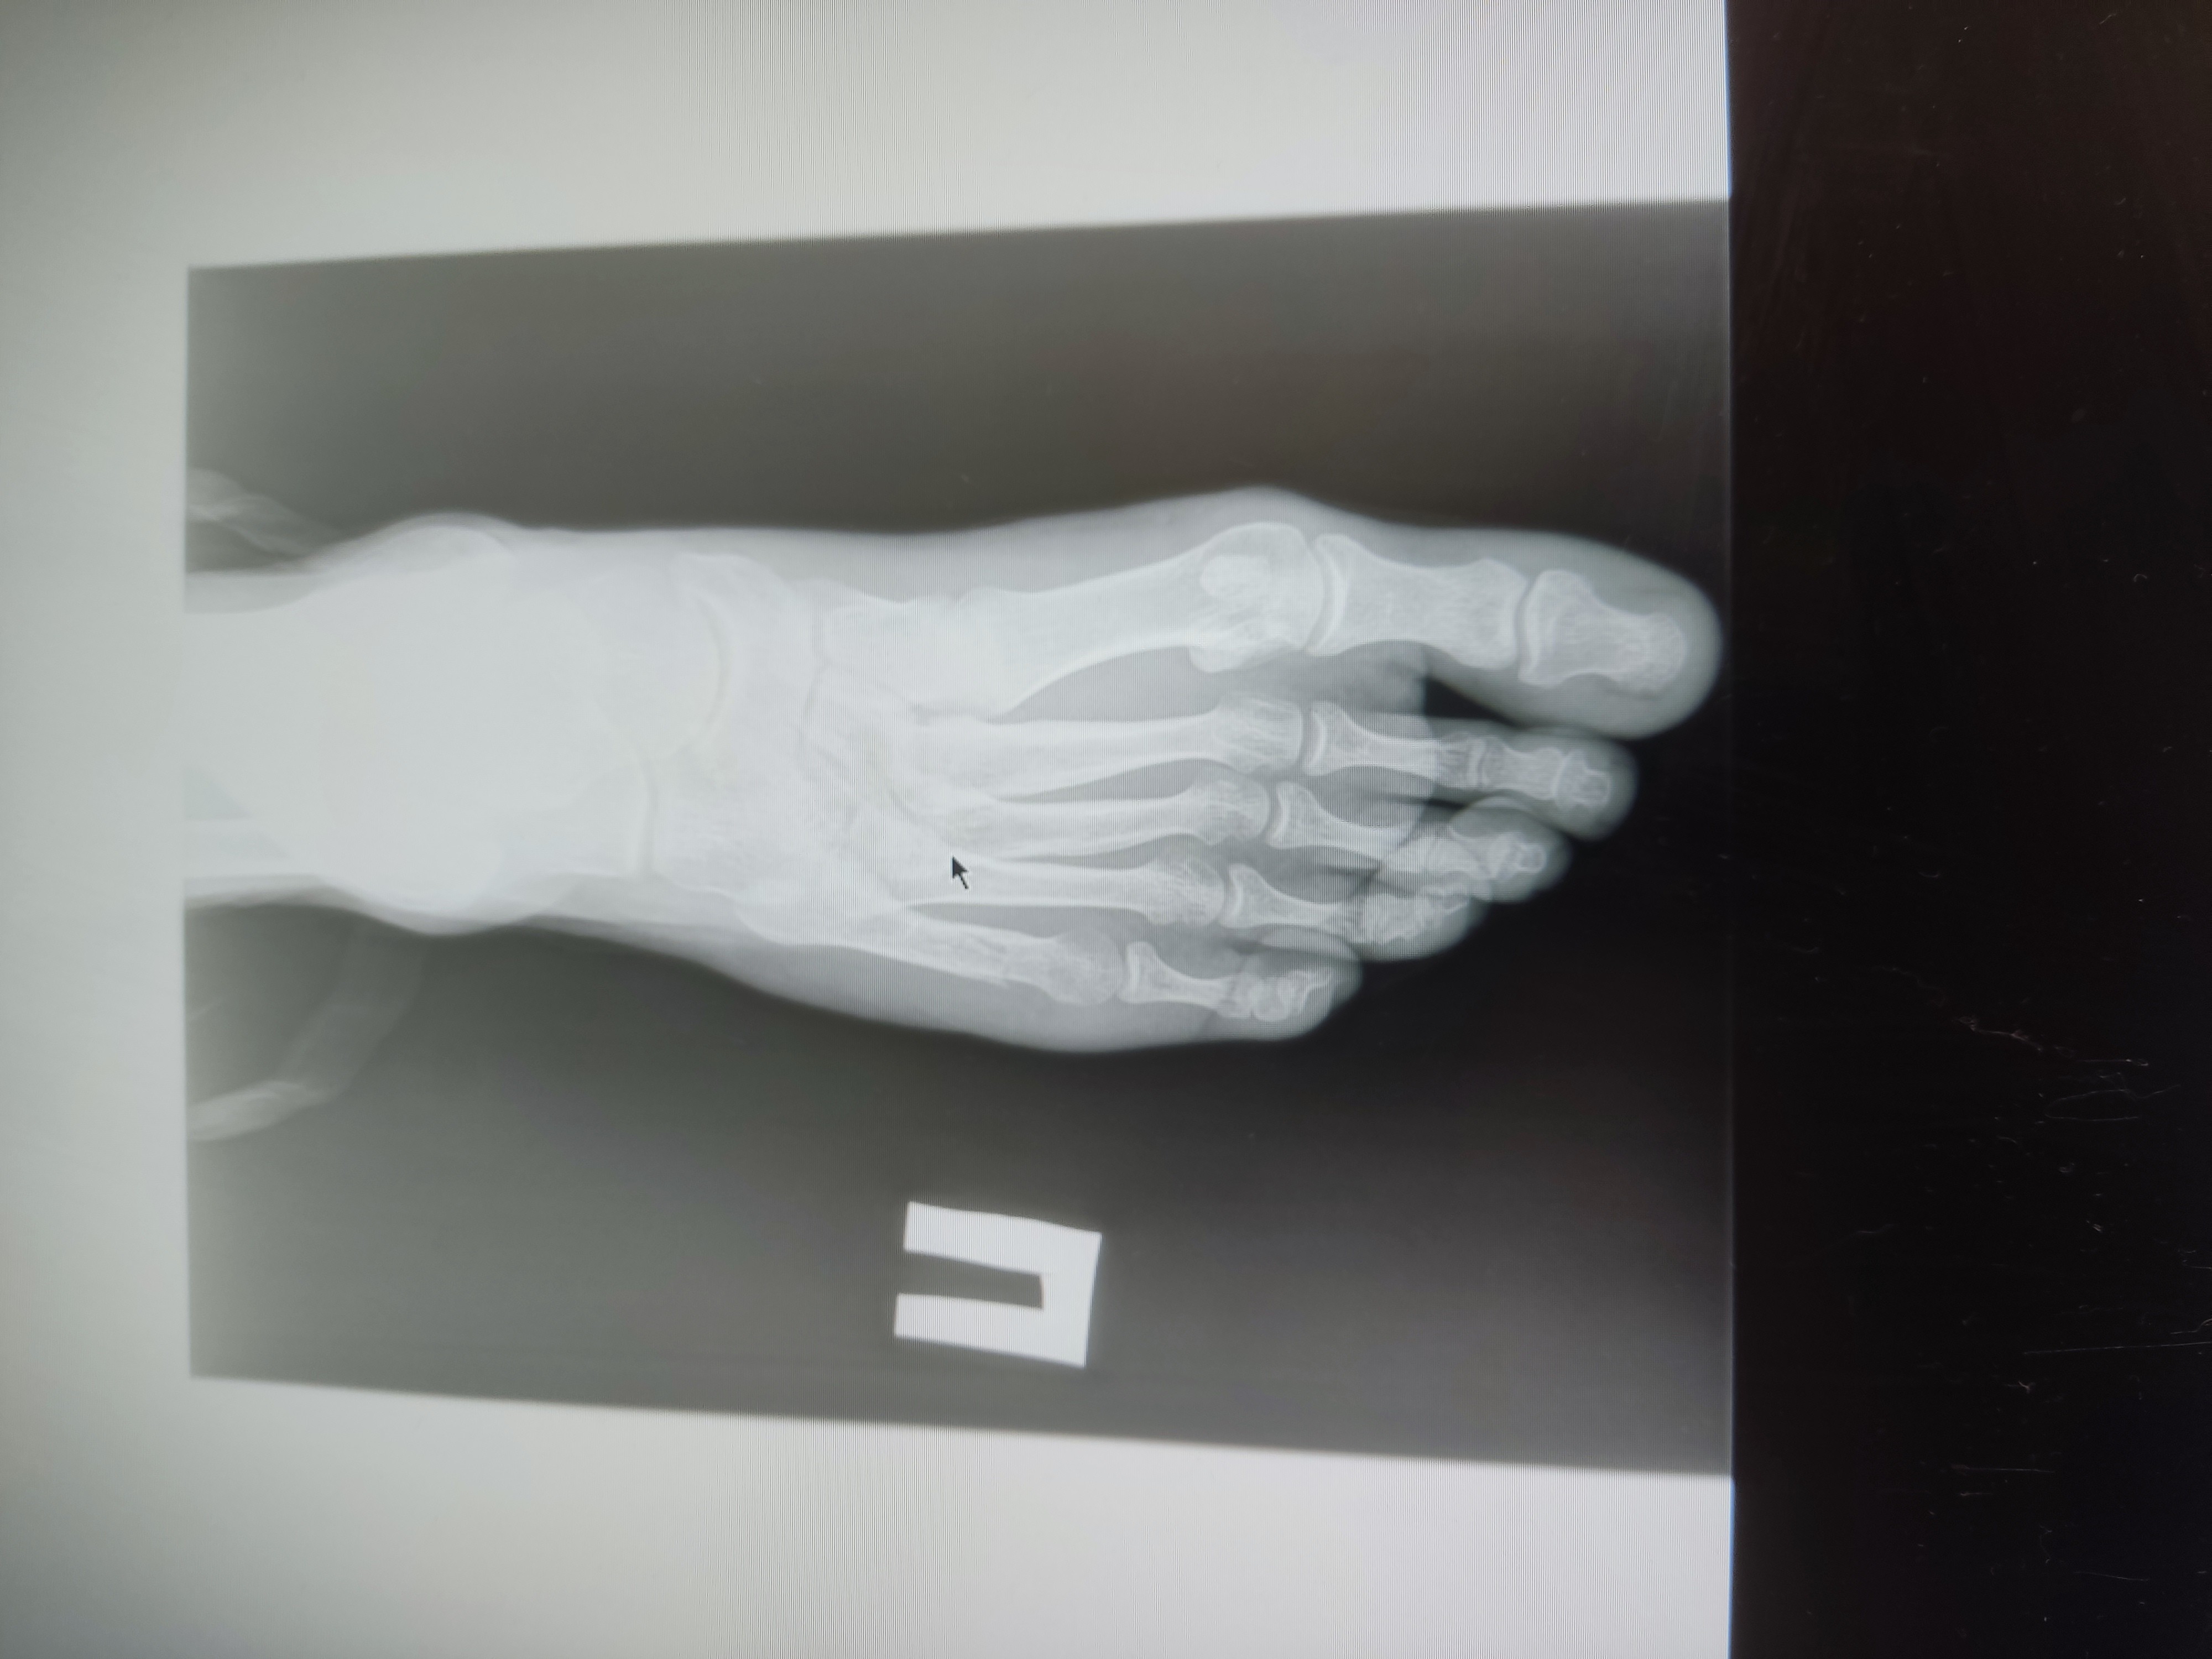

Салют, поперечное плоскостопие + 1 ст. Артроза большого пальчика)

Вкатываюсь одной ногой в тред вместе со своим заболеванием.

Анончики, не знаю в какой тред пойти, спрошу тут

На пикрил снимок спустя 14 дней после травмы.

Перелом пятой плюсневой со смешением 4мм, произошёл когда подвернул ногу, 32лвл

Гипс наложил на следующий день после травмы в травматологии травму получил в чужом городе.

Операцию не делали и ни один из двух травматологов моего и не моего города не говорил о её необходимости

Сейчас прошло 4 недели с травмы, местный врач сказала снимать гипс, врач другого города изначально говорил про 6 недель в гипсе. Назначили физио, скорее всего алмаг, точно узнаю на процедуре в понедельник

Основной вопрос — какова вероятность того, что я всю оставшуюся жизнь буду хромать?